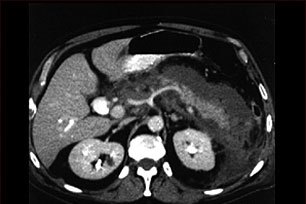

Данное изображение- это компьютерная томография верхней части брюшной полости, на которой четко диагностируется воспаление и отечность тканей поджелудочной железы, вызванной острой инфекцией (панкреатит).

• Компьютерная томография брюшной полости